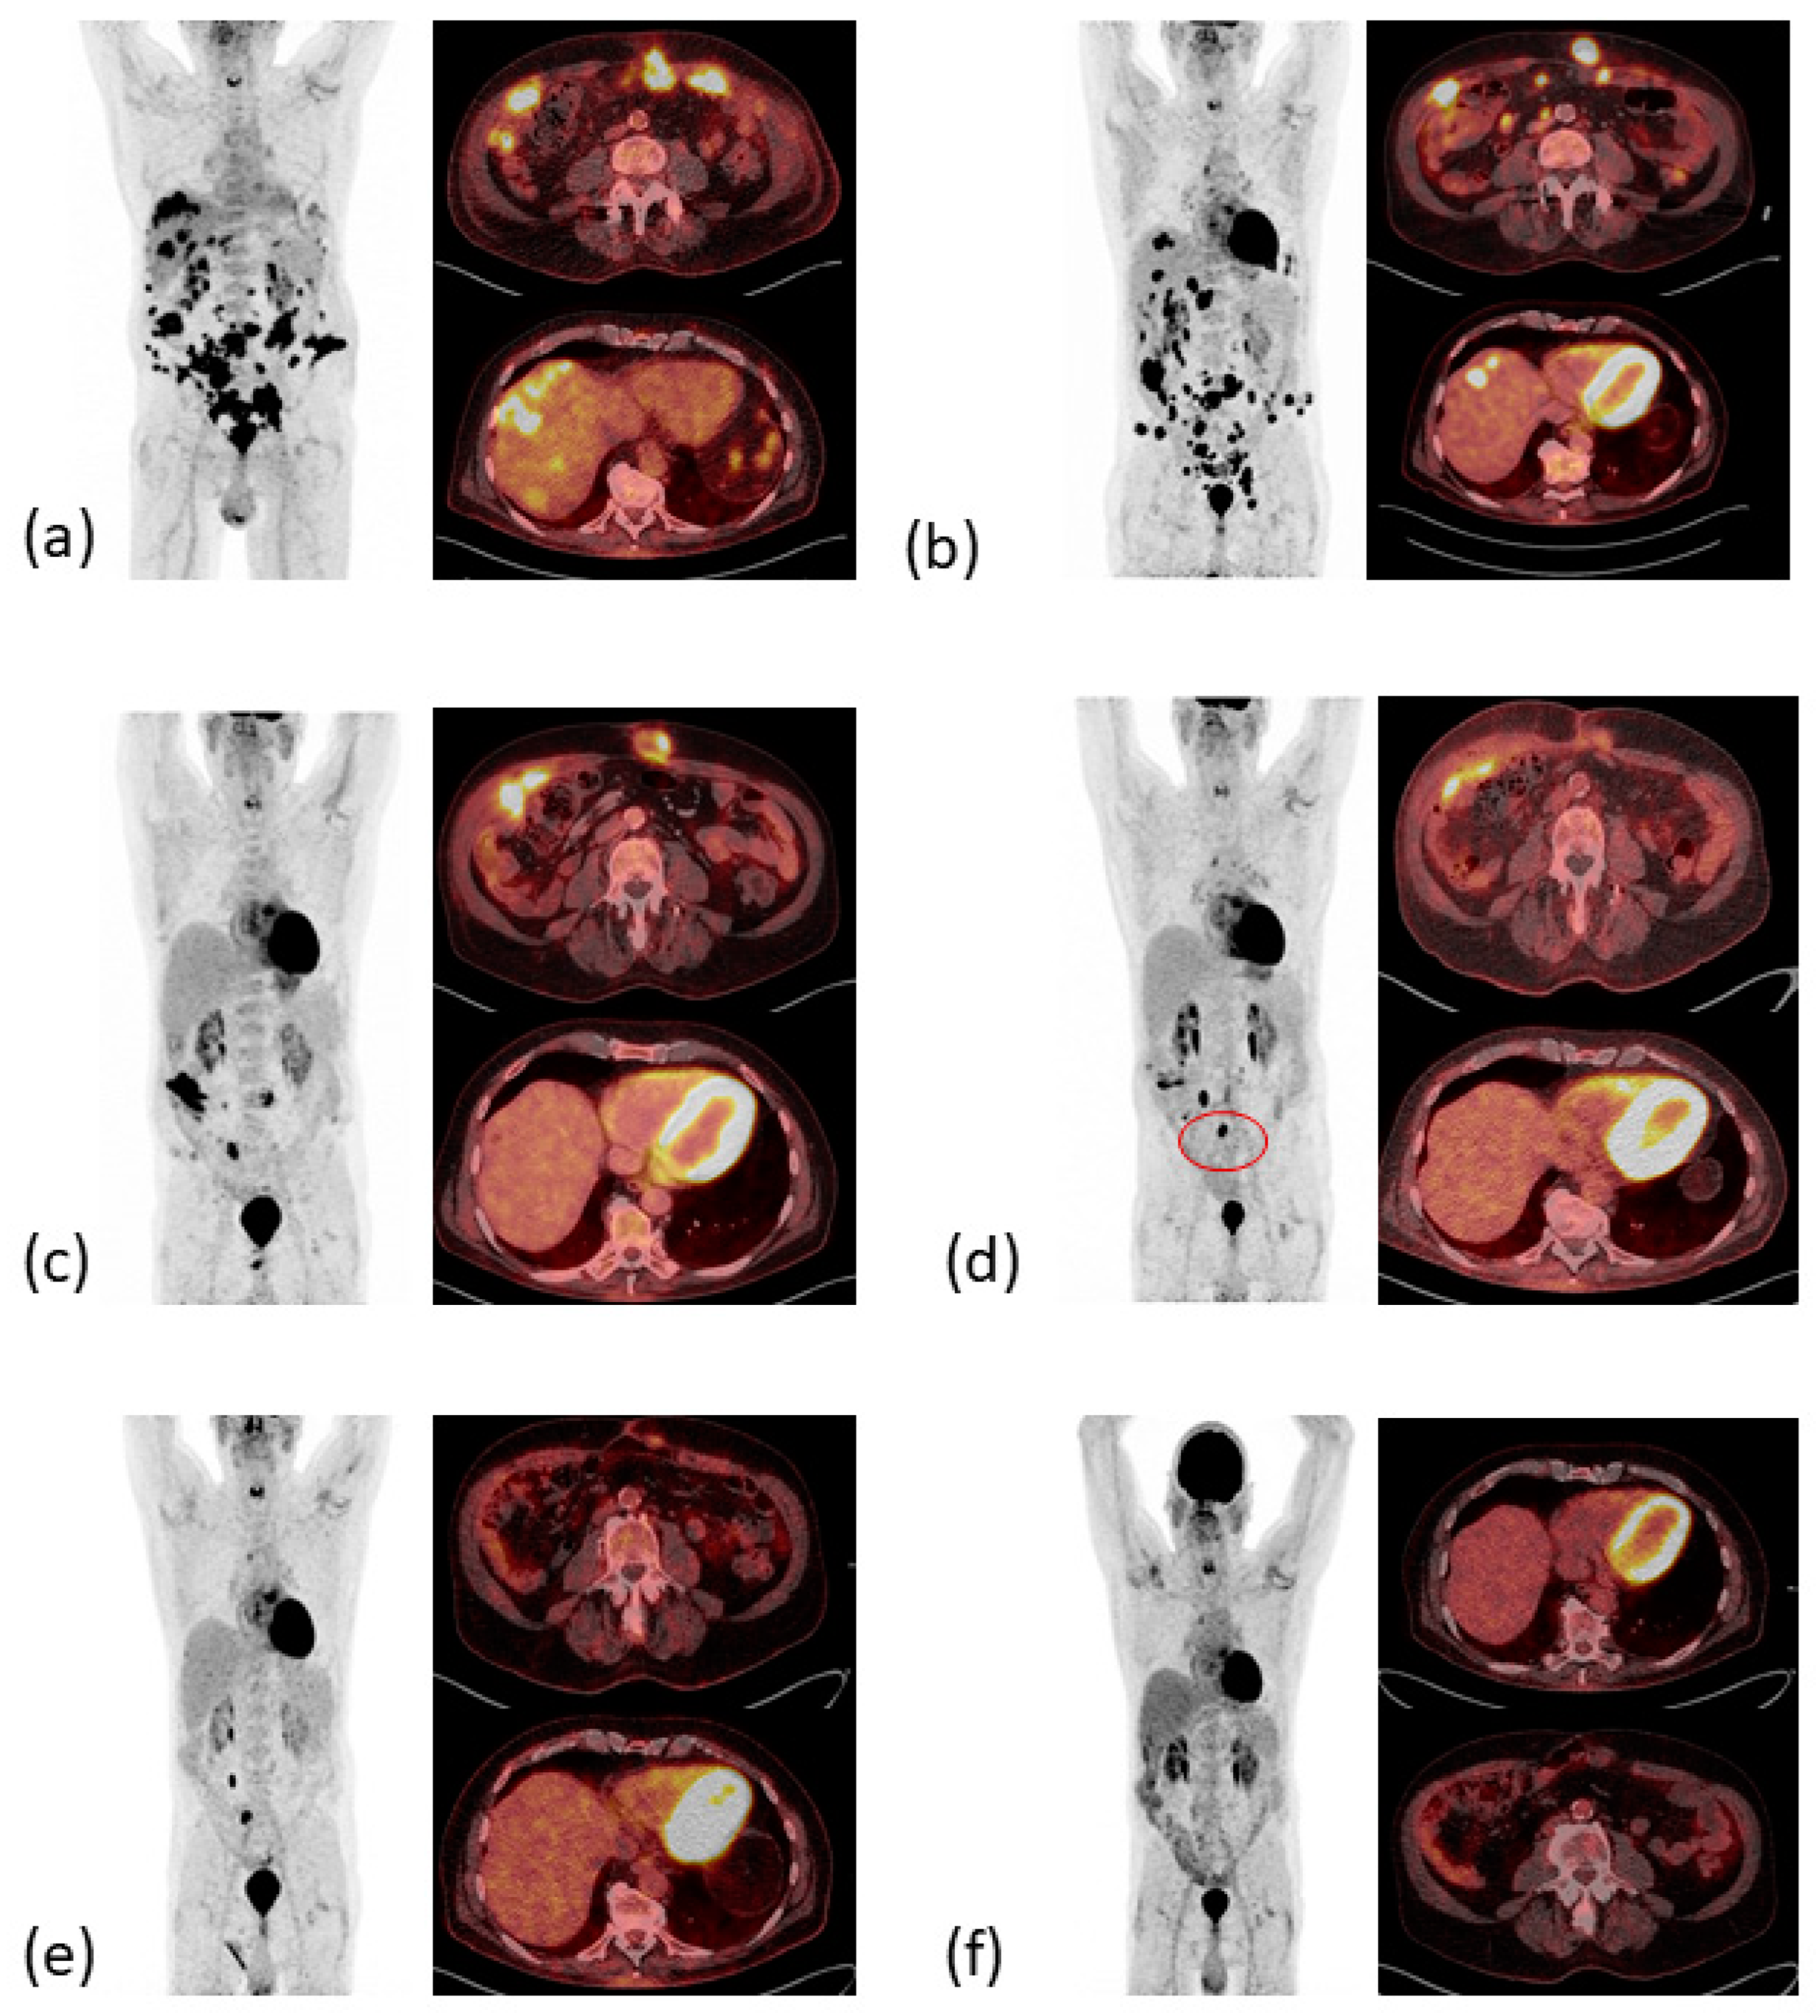

2. Case Presentation